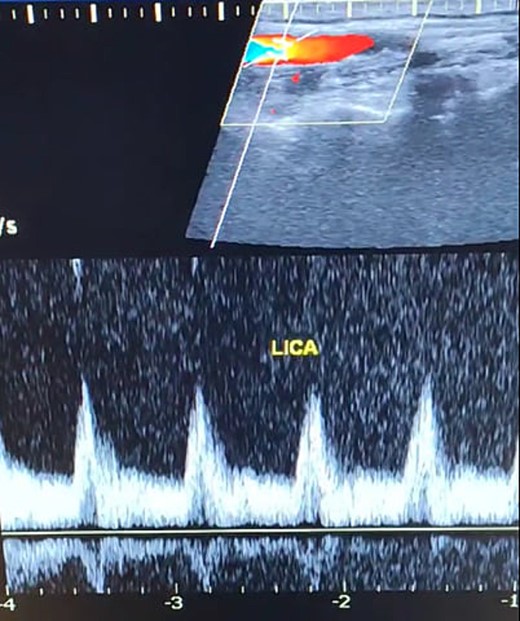

A 65-year-old male presented with recurrent transient ischemic attacks (TIAs), characterized by severe balance disturbances, transient alterations in consciousness, and visual obscurations. Clinical examination revealed high blood pressure in the right arm and absent left radial and brachial artery pulses. Vital signs were normal. Laboratory tests are analyzed as follows: urea: 22 mg/dl, glucose: 150 mg/dl, cholesterol: 199 mg/dl, and triglycerides: 222 mg/dl. A medical history of type 2 diabetes mellitus (DT2), hypertension (HTN), hyperlipidemia, ischemic heart disease, and a heavy smoking history were recorded. Five years before presentation, the patient underwent coronary stenting. Medication history included metformin 1000 mg, aspirin 81 mg, rosuvastatin 40 mg, and ramipril 5 mg. Neck duplex ultrasound (DU) showed normal flow direction and insignificant atherosclerotic plaques in the left internal carotid artery (CA) and left external CA (Figs 1 and 2), normal common CA (Fig. 3), a completely inverted flow direction in the left VA (Fig. 4) that suspected a significant ostial lesion in the left SCA. Multi-slice computed tomography angiography demonstrated 99% stenosis at the left SCA origin and confirmed the presence of SSS (Fig. 5). A balloon angioplasty was unsuccessfully attempted to expand the left SCA. A left carotid VA bypass surgery was performed, and a vascular graft was used to establish a blood flow pathway between the left VA and the left CA. By follow-up, the patient was stable without complications.

Duplex ultrasound showing a normal flow direction and insignifcant atherosclerotic plaques in the left internal carotid artery.